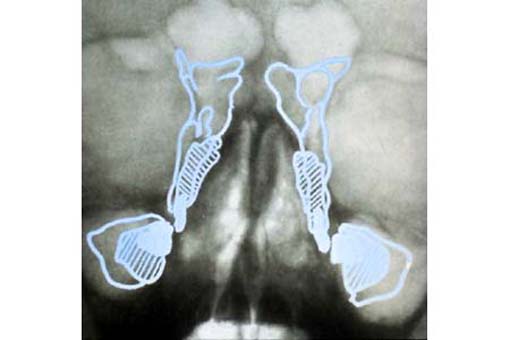

Nasennebenhöhlen . ........ Zum Kapitel